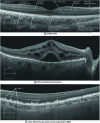

Optical coherence tomography (OCT) is micrometer-resolution imaging technique based on low-coherence interferometry. Commonly used in ophthalmology for imaging the retina and the anterior segment of the eye, OCT is beginning to be used in cardiology for the examination of the coronary arteries, as well as in gastroenterology and dermatology for the detection of tumors. This article outlines the principle of OCT, describes its technology and discusses biomedical applications. The main technological extensions of OCT giving access to functional information on tissues are presented, as well as its association with other techniques.

Optical coherence tomography (OCT) is an optical imaging technique used primarily in the biomedical field. OCT has been commercially available since 1996 for retinal imaging, just a few years after its first laboratory demonstration. It is now a standard and indispensable technique in ophthalmology. OCT is beginning to be used in other areas of medicine, notably in interventional cardiology for the treatment of coronary artery disease. By providing non-invasive, micrometer-scale images, OCT performs an "optical biopsy", making it possible to obtain information on biological tissues from imaging, instead of the conventional biopsy followed by histopathological examination. OCT is thus of interest in gastroenterology for the detection of incipient cancers, and in dermatology to improve the diagnosis of skin lesions.

Often described as the optical analogue to ultrasound, OCT probes biological tissues with light instead of ultrasound, and maps their reflectivity in depth. In ultrasound, tissue structures are localized by measuring the travel time of echoes. Because of the propagation speed of light, around 1.5.10 5 times greater than that of sound in tissue, such a measurement is not feasible in optics. An indirect measurement method is implemented in OCT, based on interferometry in weakly coherent light. After reflection by the tissue, the light beam interferes with a reference beam from the same light source. From the interferometric signal detected, we gain access to the depth reflectivity profile of the tissue, known as an "A-scan" by analogy with ultrasound. Based on several adjacent A-scans, 2 or even 3-dimensional images can be obtained. Reflective structures located at different depths can be distinguished, if their distances are greater than the coherence length of the light detected. The lower the temporal coherence of the light, the better the depth resolution in OCT. In practice, this resolution is between 1 and 20 µm. Penetration depth in biological tissue is mainly limited by light scattering. In highly scattering media, such as skin, it is around 1 mm. This penetration is superior to that of other high-resolution optical imaging techniques such as confocal microscopy.